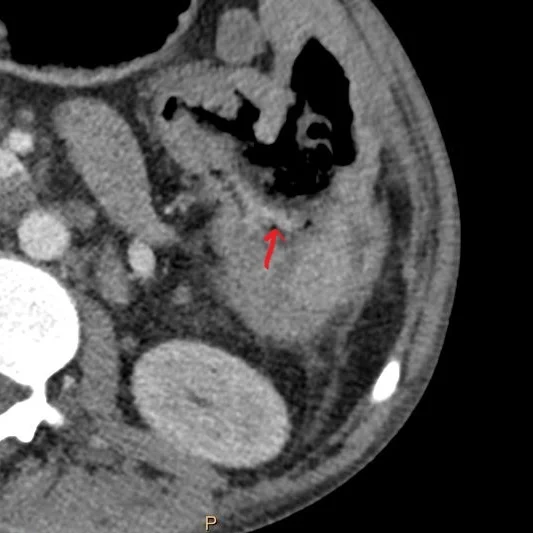

Conventional CT (axial plane) shows ill-defined density (red arrow) in the posterior aspect of fistula

Ill-defined density in the posterior aspect of the fistula shows clear iodine uptake and is consistent with active GI bleed. Patient was stabilized and taken to the operating room, with extensive surgery confirming B-cell lymphoma.